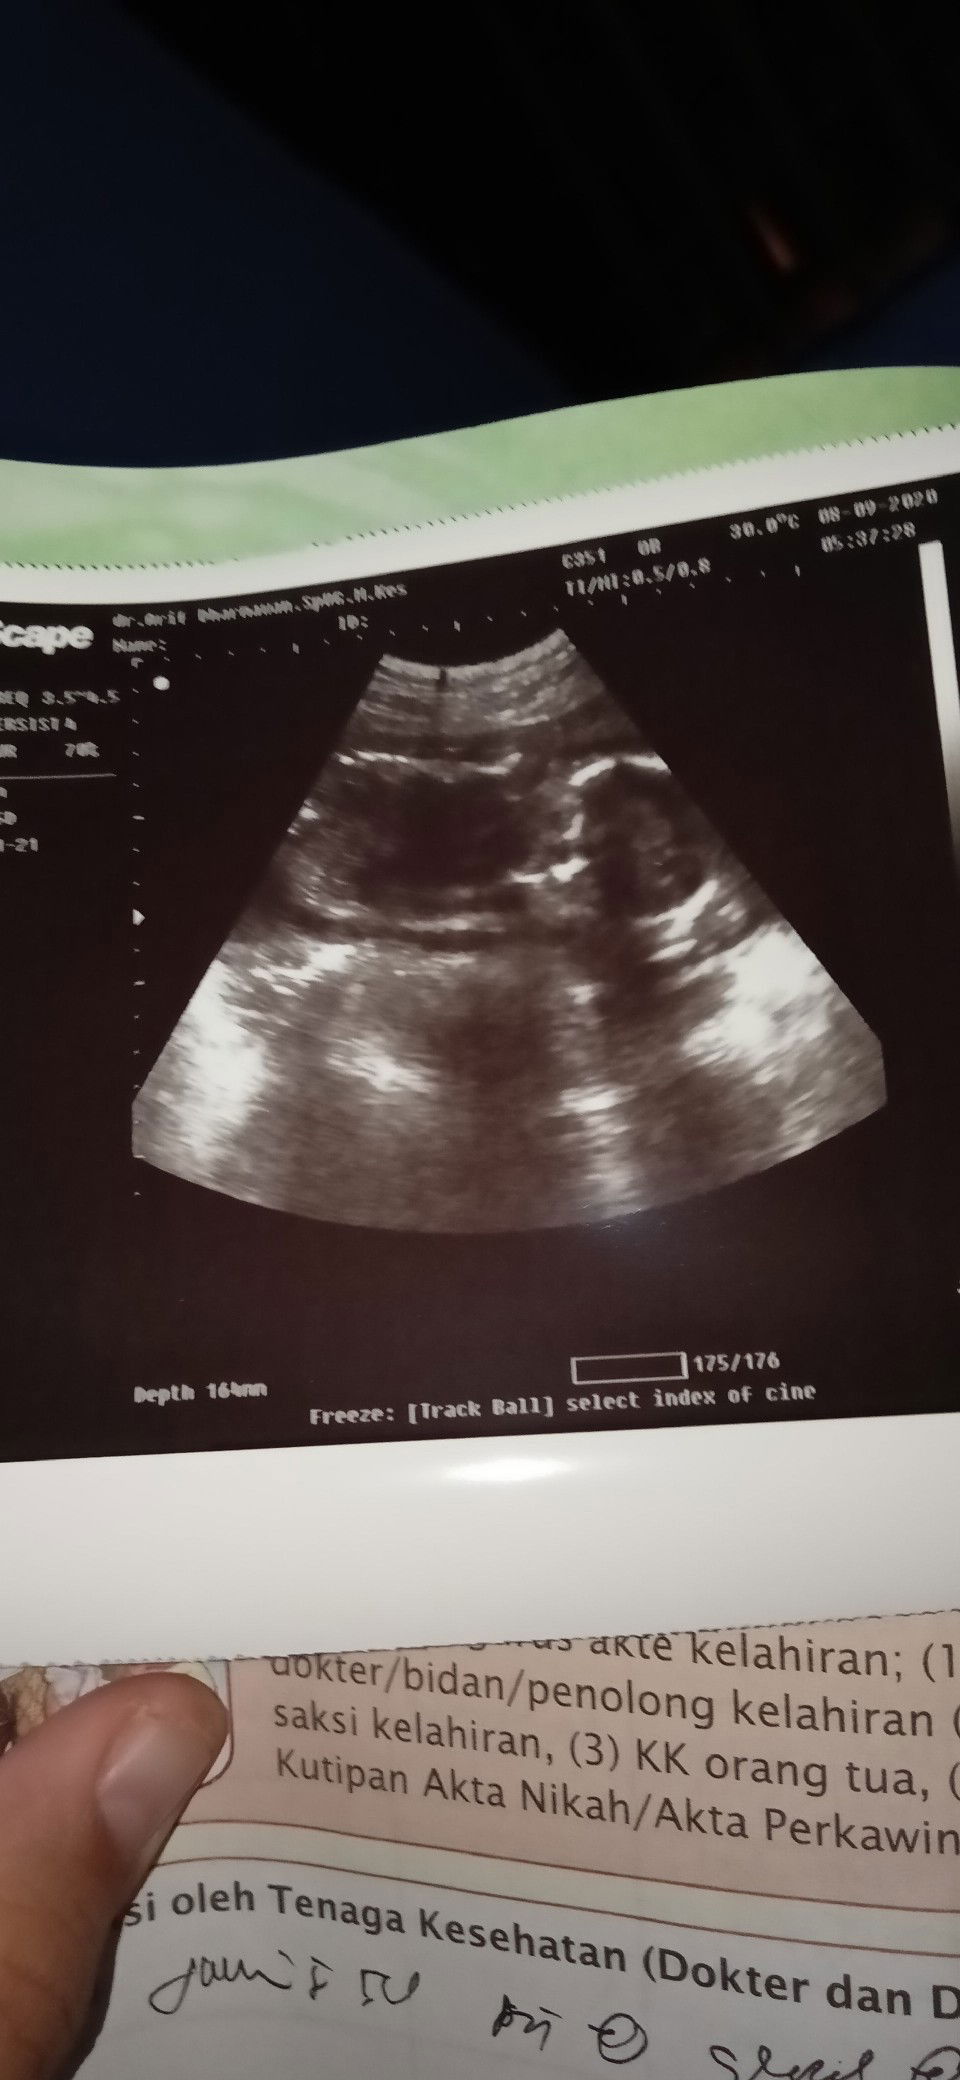

19 week 4 day hpl 9 mei bun dan alhamdulillah udh ngrasain debaynya nendang😁